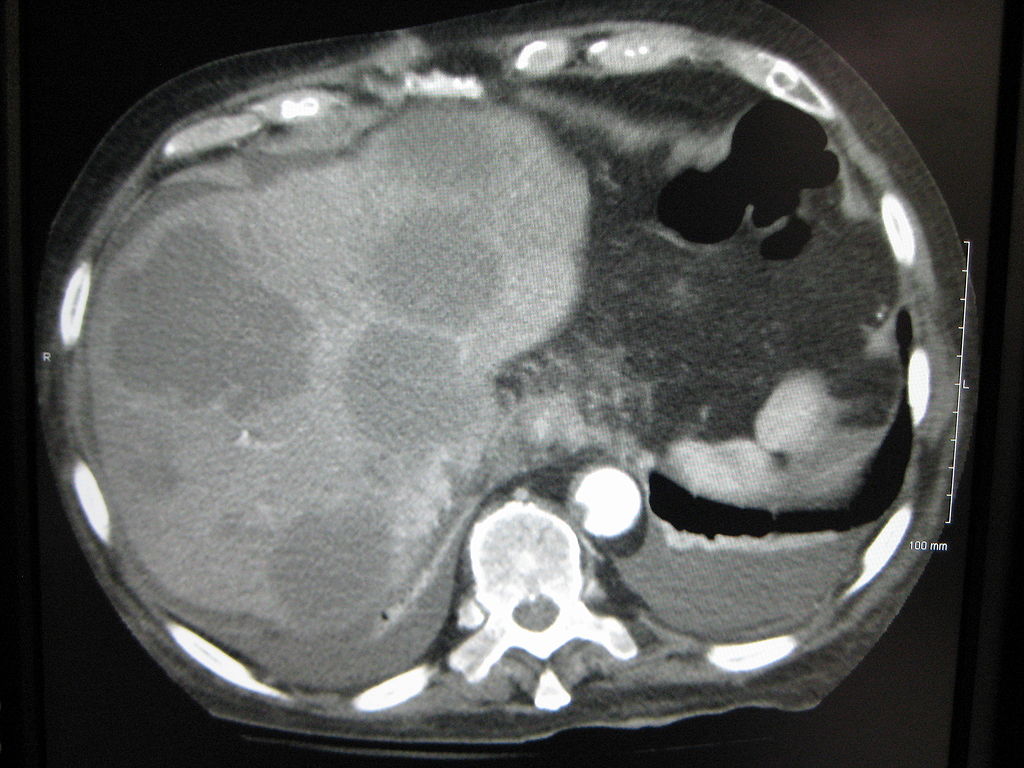

| Axial CT of the abdomen showing multiple liver metastases. Image courtesy of James Heilman, MD / Wikimedia Commons / CC-BY-SA-3.0 |

The majority of liver metastases present as multiple tumors. Only 10% of all cases present with a solitary metastatic lesion. Moreover, in more than three-quarters (3/4) of patients with liver metastases, there is involvement of both lobes of the liver.